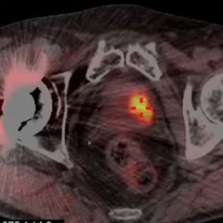

Le TEPSCAN (Tomographie par Émission de Positons) ou PET SCAN est une technique d’imagerie médicale de médecine nucléaire permettant de réaliser une image fonctionnelle reposant sur l’injection intraveineuse d’un radiotraceur, le FDG (FluoroDeoxyGlucose) le plus souvent.

L’appareil d’imagerie comporte 2 machines associées (imagerie hybride) : le TEP permettant de recueillir les rayonnements gamma émis par le patient et un scanner (TDM) émettant des rayons X d’où le nom de TEP-TDM.